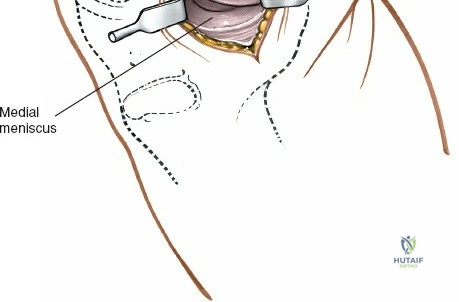

Exposure of the Meniscus:

- Retractors are carefully placed to expose the medial tibiofemoral compartment. Self-retaining retractors may be used, but care must be taken to protect the articular cartilage.

- To improve visualization, the knee is brought into hyperflexion (as per seed content, "beyond a right angle"). This maneuver, combined with external rotation of the tibia and a valgus stress applied to the knee, widens the medial compartment. This allows for improved access to the posterior horn of the medial meniscus.

Meniscectomy Technique (Partial):

- Inspection: Thoroughly inspect the medial meniscus to identify the tear pattern and assess its stability using a blunt probe.

- Resection: The goal is partial meniscectomy, removing only the unstable, symptomatic fragment. Total meniscectomy is strongly discouraged due to long-term sequelae.

- Specialized meniscal knives (e.g., banana knife, hook knife) are used to make precise cuts, detaching the torn fragment from the stable meniscal rim and meniscocapsular junction.

- Small rongeurs or basket forceps are then used to excise the torn portion.

- The remaining meniscal edge is carefully contoured and smoothed to prevent any residual tags from impinging or causing further irritation.

- "Removal of loose bodies" and "Removal of foreign bodies" are also performed at this stage if identified, utilizing the direct visualization offered by the open approach.

Closure:

- Irrigate the joint thoroughly.

- Carefully repair the joint capsule and deep fascia using absorbable sutures. This helps restore joint stability and minimize synovial fluid leakage.

- Close the subcutaneous tissue layer.

- Close the skin with non-absorbable sutures or staples.

- A sterile dressing is applied. Drainage is typically not necessary for uncomplicated partial meniscectomy but may be considered if significant bleeding is encountered or with a larger arthrotomy.